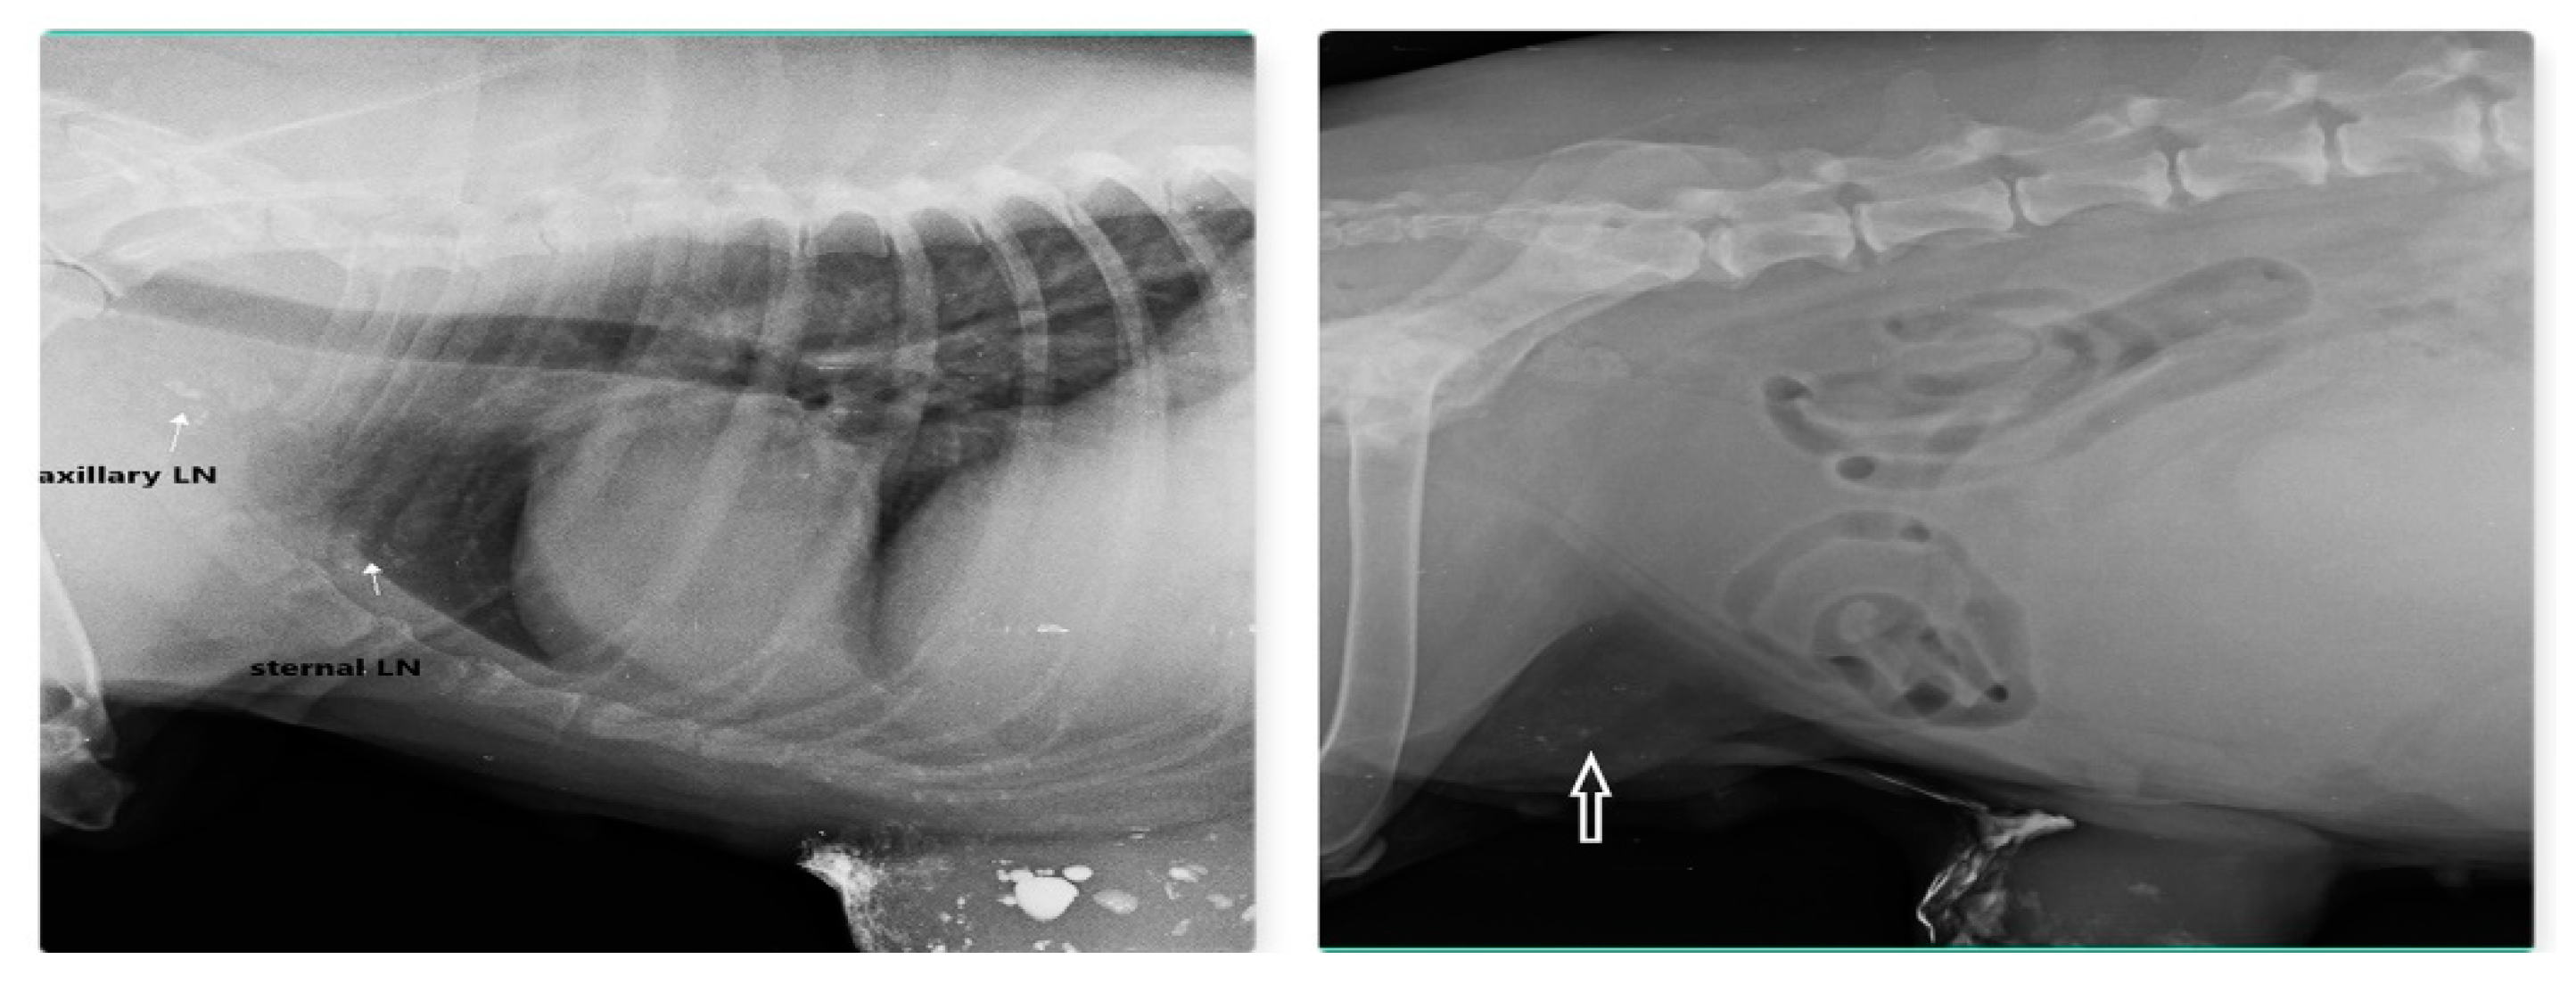

Out of 23 cases of mammary carcinoma, IL with MB dye procedure detects 12 SLN, IL with Lipiodol detects 9 SLN and IL with iohexol is able to detect SLN in 2 cases. Carcinoma was found in both sides from 2nd to 5th mammary gland (MG) but not in 1st MG. Preoperative IL with Lipiodol injection was performed in 9 primary mammary carcinomas via intradermal and subcutaneous routes, led to localization of nine SLN (lymphoid plexus of thigh –two, inguinal-four, axillary –two, and sternal-one). IL with Lipiodol in mammary carcinoma of 2nd MG and subsequent radiograph after 24hour detected sternal lymph node as SLN and axillary LN as second tier node after 48hour is shown in Fig. 12. Post injection radiographs are monitored in 5 patients up to 21 days with similar LN visibility

Figure 12. Sternal LN as SLN for carcinoma of 2nd and 3rd MG (left) and inguinal LN (arrow) as SLN for carcinoma of 4th and 5th MG (right) detected through indirect radiographic lymphography with Lipiodol.

Preprints 77141 g012